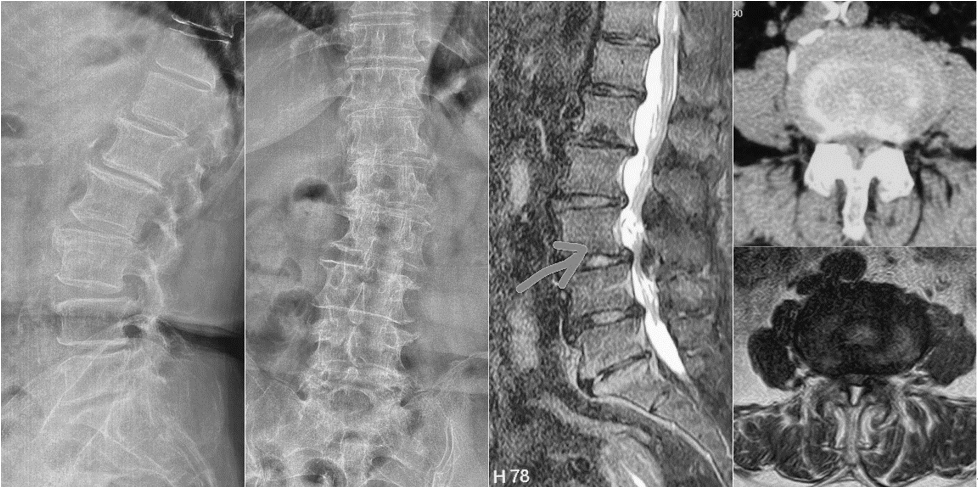

第三例51岁女性患者,因“右下肢放射性疼痛、麻木1年,加重1月余”入院,发病以来反复多次保守治疗无效。入院后经术前讨论、评估,制定治疗方案,行OLIF手术,该病例采用后路经皮椎弓根螺钉内固定。次日患者下地活动,下肢症状消失,疗效满意。

术前影像